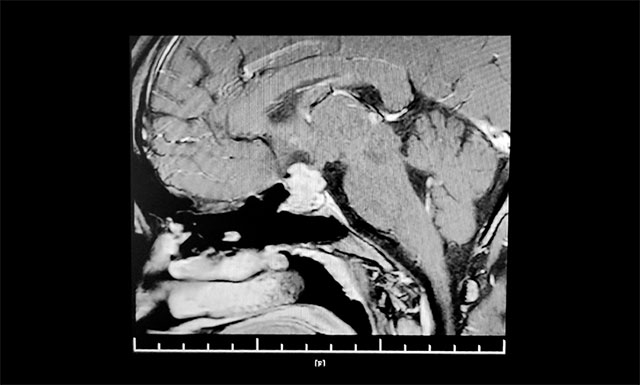

▲ 术前影像:垂体大腺瘤,向鞍上生长

鞍区MRI平扫+增强显示:蝶窦显著扩大,鞍区见肿块影,鞍膈初见“腰征”,灶区矢横高径约1.8*2.0*2.0mm。病变向鞍上生长,占据鞍上池,推移视交叉。

上海蓝十字脑科医院神经外科6B病区主任潘仁龙指出,垂体肿瘤向鞍上生长,占据鞍上池,压迫到视神经传导物,使患者视物出现异常。一般1-3cm的大腺瘤或大于3cm的巨大腺瘤,都会引起不同程度的视力问题。